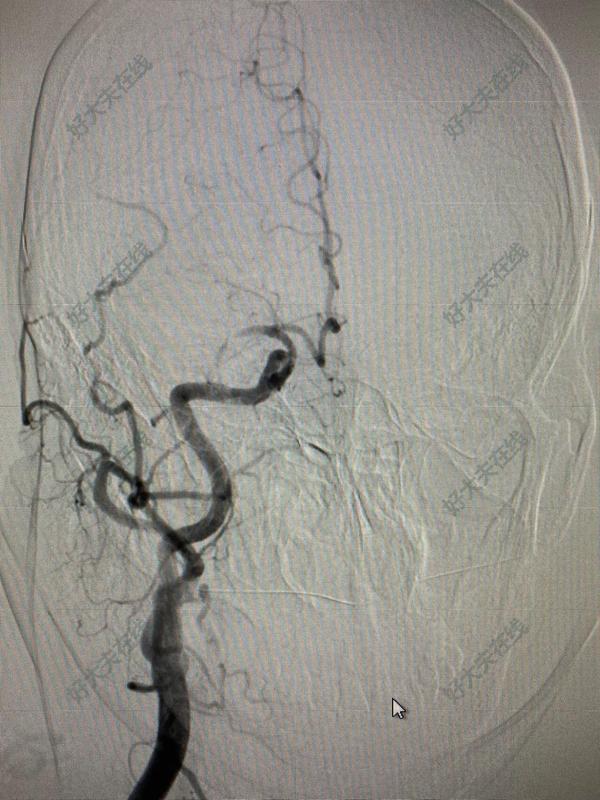

女性患者67歲,右側(cè)基底節(jié)區(qū)腦梗塞,導(dǎo)致左側(cè)肢體偏癱。經(jīng)過一段時間的康復(fù)治療后,癱瘓一側(cè)的肢體略微有所好轉(zhuǎn),下肢可以輕微移動一些,但上肢仍然是完全不能活動。做腦血管造影發(fā)現(xiàn)右側(cè)大腦中動脈起始段完全閉塞,右側(cè)大腦半球較為廣泛的灌注減低。由于患者右側(cè)大腦半球缺血,但仍有緩慢而微弱的好轉(zhuǎn),結(jié)合CT灌注說明下肢肌力有略微好轉(zhuǎn),但仍不能行走,上肢肌力無法活動。為改善缺血側(cè)腦血流并防止由于局部缺乏足夠的血運(yùn)導(dǎo)致腦缺血進(jìn)一步加重。我們?yōu)榛颊哌M(jìn)行了小切口、微創(chuàng)的顳淺動脈-大腦中動脈搭橋(STA-MCA bypass)。手術(shù)采取小直切口,切開頭皮,分離出顳淺動脈,做為供血血管。然后開顱做一個大小3-4cm的骨瓣暴露腦表面的大腦中動脈的分支,分離出直徑1mm的供血動脈。顳淺動脈和大腦中動脈之間在顯微鏡下做端-側(cè)吻合。術(shù)中熒光造影(ICG)檢查吻合處血流通暢。由于創(chuàng)傷極小,因此,術(shù)后第二天完全可以下床進(jìn)行正常飲食和活動,術(shù)后CTA顯示顳淺動脈和大腦中動脈吻合通暢,手術(shù)效果滿意。第三天患者順利出院,繼續(xù)康復(fù)治療。顳淺-大腦中動脈搭橋術(shù) (STA-MCA)是常用的直接血管重建方法,通過顯微外科的方法將顱外顳淺動脈“分流”到顱內(nèi)腦表面的大腦中動脈上,達(dá)到直接促進(jìn)腦組織血流目的。對于閉塞性腦血管疾患、反復(fù)短暫性腦缺血發(fā)作,本手術(shù)可防止或減少其發(fā)作。對于那些由于大腦中動脈閉塞造成的缺血性神經(jīng)損害、完全性卒中等,血管搭橋無疑為這類患者提供了避免偏癱、失語等進(jìn)一步加重,甚至逐步恢復(fù)的機(jī)會。臨床結(jié)果也證明,對煙霧病等因頸內(nèi)動脈閉塞導(dǎo)致的供血不足或腦梗塞,顳淺動脈-大腦中動脈搭橋是目前最行之有效的方法。經(jīng)典的手術(shù)方法需要弧形切開皮膚及筋膜瓣,分離出顳淺動脈,經(jīng)顳頂部開顱,在皮層上選擇合適的受體血管。微創(chuàng)手術(shù)方法,切口和開顱的骨瓣明顯小于傳統(tǒng)方法,盡管會限制手術(shù)視野的暴露,對手術(shù)器械和技術(shù)的要求更高,但圍手術(shù)期并發(fā)癥發(fā)生率較低,小骨窗開顱可以有效避免術(shù)后硬膜外和硬膜下血腫的發(fā)生,同時可以最大可能的減少蛛網(wǎng)膜瘢痕的形成。而且顯而易見的是,這類病人術(shù)后的恢復(fù)時間明顯要快很多,往往2-3天就能康復(fù)出院。大腦中動脈閉塞而導(dǎo)致的腦?;颊咄俭w弱多病,患有高血壓、糖尿病、冠心病等多種合并癥,且常常伴有偏癱、肺部感染等情況。因此手術(shù)損傷小、術(shù)后恢復(fù)快的方法就顯得更加重要了,能夠以最小的代價,換取最大的收益。

昨天我們講了蛛網(wǎng)膜下腔出血的前因后果。其中需要診斷動脈瘤就需要進(jìn)行腦血管造影。這就涉及到了神經(jīng)介入技術(shù)。在很多人看起來神經(jīng)介入治療是一項(xiàng)高大上的技術(shù),充滿著神秘感。實(shí)際上您如果了解該技術(shù),它一點(diǎn)也不神秘。在我們科室這是一項(xiàng)常規(guī)技術(shù),就拿昨天來說吧,我們一共排了14臺手術(shù),全部完成已經(jīng)達(dá)到了凌晨2點(diǎn),雖然累,但是大家看到患者的滿意笑容,還是感覺很值得的。好了,今天我們就來揭秘這項(xiàng)目前在神經(jīng)科領(lǐng)域最火熱的一項(xiàng)技術(shù)。1.什么是介入治療?介入治療是在X-線監(jiān)視下,從大腿根部切開約2毫米的切口,置入鞘管,然后通過鞘管使用導(dǎo)管插入到相應(yīng)的腦動脈,通過導(dǎo)管做診斷和治療。打個比方,人體的血管就像是縱橫交錯的管道,當(dāng)管道出現(xiàn)狹窄或堵塞時,需要派遣一個清潔工人去疏通管道。而介入治療就是將不同工種的工人,在輔助工具的輔助之下通過這些“河道”運(yùn)送到堵塞處,再根據(jù)病變的性質(zhì),采用不同的方法,如注藥、球囊擴(kuò)張、置入支架等操作疏通血管,達(dá)到治療目的。2.腦血管造影是一種什么檢查?腦血管造影廣泛應(yīng)用于臨床的一種嶄新的X線檢查新技術(shù),即數(shù)字化減影血管造影術(shù),簡稱DSA,一般是在右側(cè)股動脈放置一動脈鞘,通過該動脈鞘管選用不同導(dǎo)管,在導(dǎo)絲引導(dǎo)下,逐步進(jìn)入所有腦血管,注入含碘造影劑,連續(xù)拍片,清晰顯示血管。DSA能清楚地顯示動脈管腔大小、狹窄、閉塞、側(cè)支循環(huán)建立與否等情況,是目前公認(rèn)的腦血管檢查的“金標(biāo)準(zhǔn)”。任何一項(xiàng)醫(yī)療操作都存在一定風(fēng)險(xiǎn),腦血管造影一般在局麻下完成,操作簡單,時間短,安全性相對較高。患者術(shù)前不需要禁食,可以完全按照日常生活進(jìn)行打針吃藥。那些患者需要進(jìn)行腦血管造影:(1)缺血性腦血管?。盒枰鞔_腦梗死,短暫性腦缺血發(fā)作,椎-基底動脈供血不足是否存在腦動脈狹窄等。(2)蛛網(wǎng)膜下腔出血:為了明確是否存在顱內(nèi)動脈瘤或血管畸形等。(3)不明原因頭痛:明確是否存在動脈瘤、靜脈竇血栓等。3.如果存在腦血管狹窄或閉塞應(yīng)該怎么辦?如果血管狹窄較輕不需要進(jìn)一步介入治療,但是需要長期應(yīng)用阿司匹林、他汀類藥物治療,正規(guī)治療高血壓、糖尿病、心臟病等疾病,并清淡飲食,戒煙限酒,適度鍛煉,保持良好心態(tài)。如果存在嚴(yán)重狹窄,就需要進(jìn)行支架治療。就是在狹窄的血管腔內(nèi)植入支架,使狹窄的血管管徑恢復(fù)正常,從而使缺血腦組織恢復(fù)正常血流,另外植入支架后使狹窄部位粗糙的血管壁重新修復(fù),防止動脈粥樣硬化斑塊的脫落和血栓形成。如果存在腦血管閉塞,且時間較短,可以進(jìn)行腦血管再通。就是將微導(dǎo)管經(jīng)血管內(nèi)直接插到血栓部位使用機(jī)械性碎裂、支架取栓或局部給溶栓藥物在最短時間內(nèi)開通血管,達(dá)到內(nèi)科治療無法達(dá)到的治療效果。輕度狹窄血管不需要支架治療重度狹窄血管需要支架治療閉塞血管可以血管開通4.腦動脈狹窄支架治療是一種什么治療?腦動脈狹窄是缺血性腦血管病最常見的原因。它也是通過股動脈穿刺,導(dǎo)管放置于狹窄部位,根據(jù)狹窄血管不同可預(yù)先于動脈狹窄處的遠(yuǎn)端置入腦保護(hù)傘,然后將球囊放置狹窄部位擴(kuò)張,之后支架植入狹窄的動脈內(nèi),支撐狹窄部位,使血流通暢,改善腦組織血供。因而其創(chuàng)傷較小,恢復(fù)快,對于那些身體條件差、年齡大的患者尤其適用。5.血管介入檢查及治療后有啥特殊要求?常規(guī)血管介入檢查及治療后需要術(shù)后3小時拔動脈鞘管,臥床并穿刺側(cè)肢體伸直位24小時,穿刺部位加壓包扎,鹽袋壓迫8小時,同時需要按摩下肢肌肉,預(yù)防血栓形成?;颊咭部梢赃x擇血管縫合器縫合穿刺部位血管,這樣就可以在臥床3-4小時后下床活動,不影響患者生活,避免了長時間臥床的痛苦。所有患者3天需要避免傷口接觸水,3天后自己揭掉膠帶,恢復(fù)日常生活。6.接受了腦血管支架治療是否還需要用藥治療?對于腦血管病患者來說,為了預(yù)防再次發(fā)生必須長期服藥,接受血管支架治療后患者也需要藥物治療,同時有以下注意事項(xiàng):低鹽低脂飲食;控制血糖,監(jiān)測血壓變化;適度鍛煉;保持良好心態(tài)。本文系王虎清醫(yī)生授權(quán)好大夫在線(bdsjw.cn)發(fā)布,未經(jīng)授權(quán)請勿轉(zhuǎn)載。